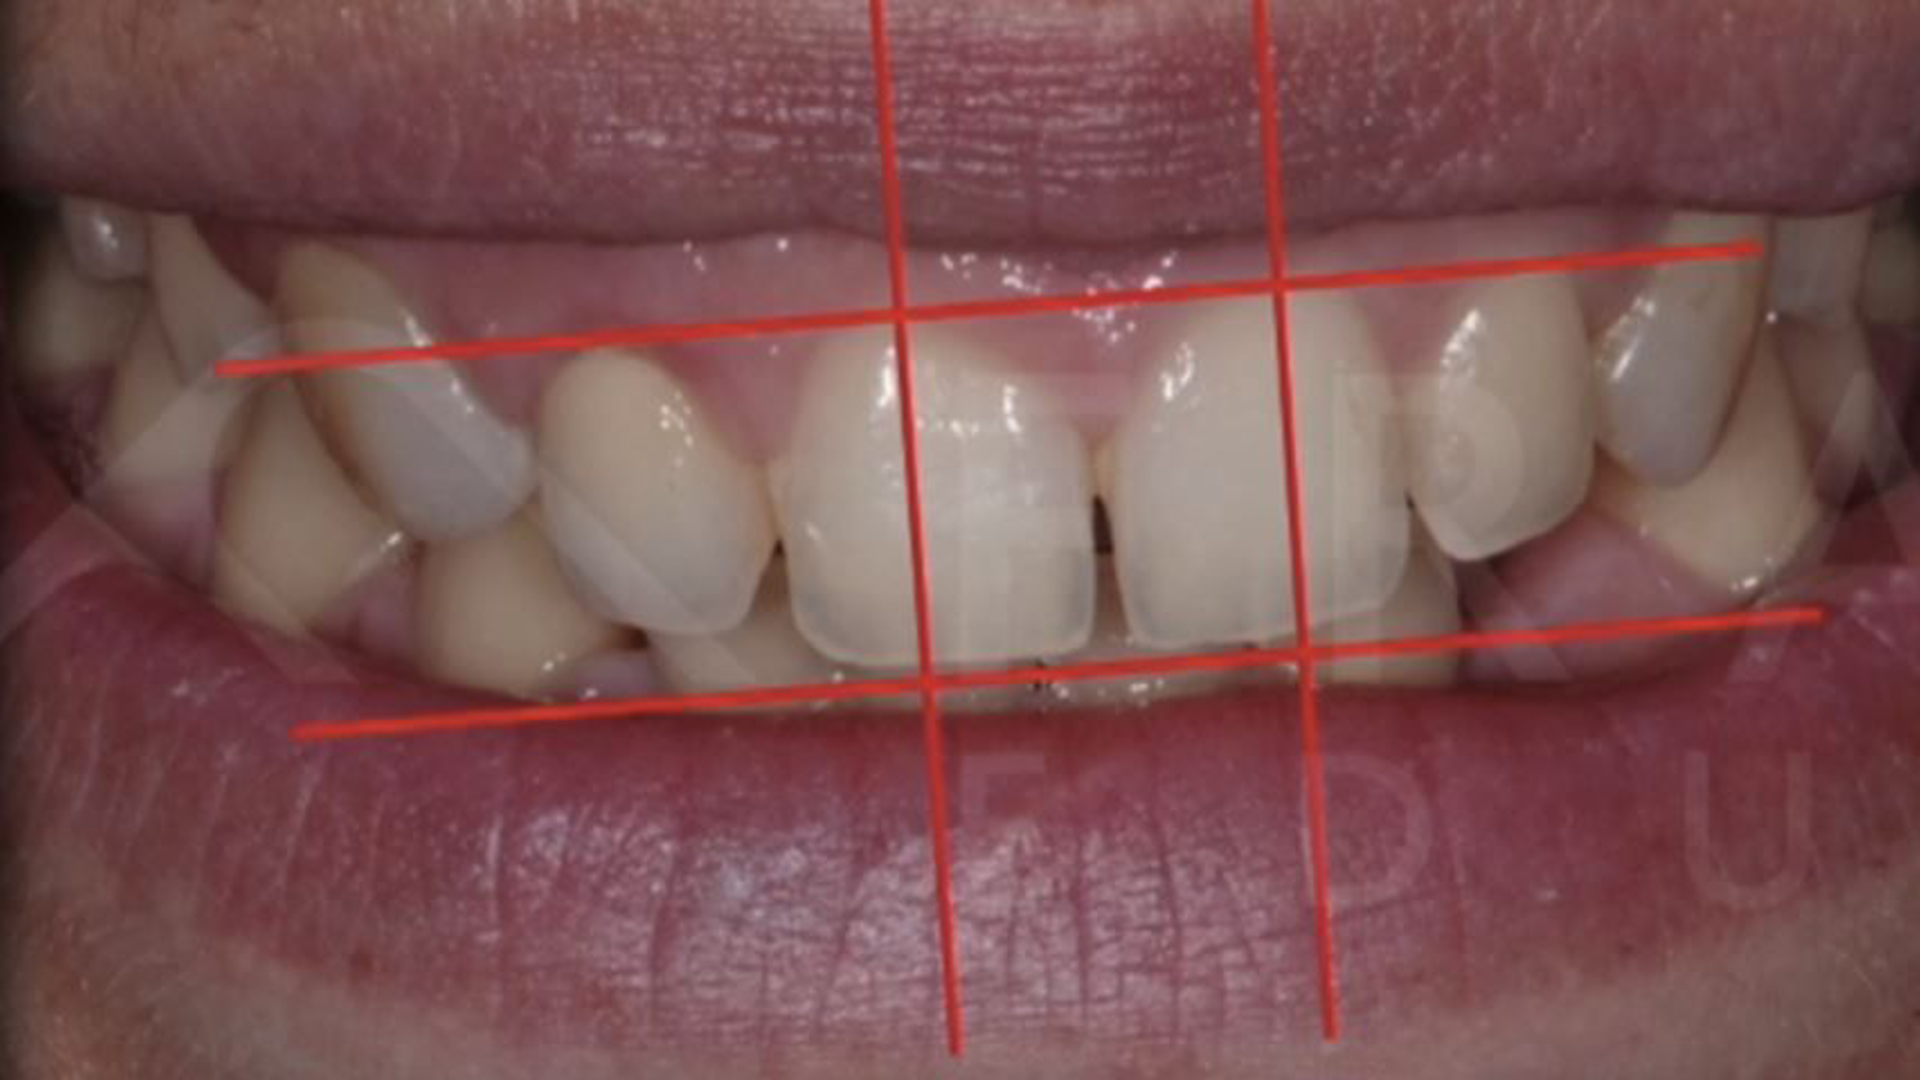

Esthetic analysis: facial analysis in prosthetic rehabilitation

Esthetic analysis: dentolabial analysis in prosthetic rehabilitation